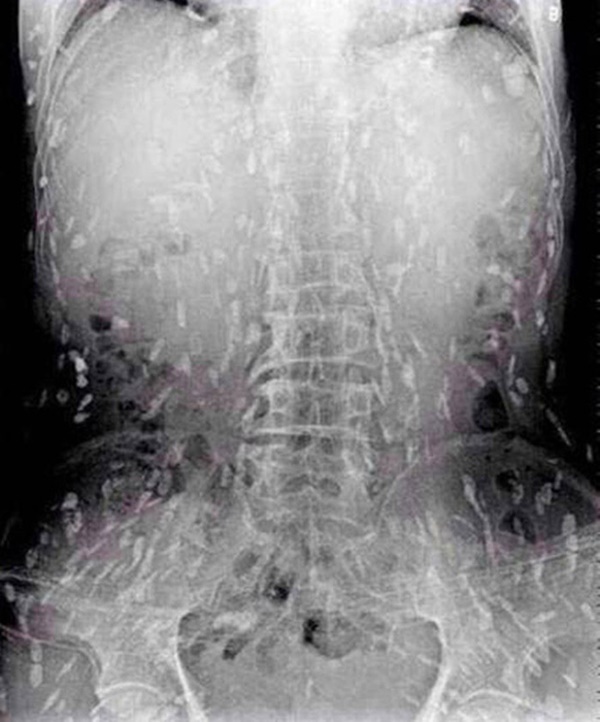

Tuy nhiên, do bệnh tình đã bước sang giai đoạn nghiêm trọng nên người đàn ông tiếp tục được chuyển tới Bệnh viện Nhân dân số 8 ở Quảng Châu để điều trị. Kết quả chụp X-quang cho thấy, những đốm trắng nhỏ xuất hiện lấm chấm khắp cơ thể chính là sán.

Những chấm trắng xuất hiện trên hình chụp X-quang là sán.